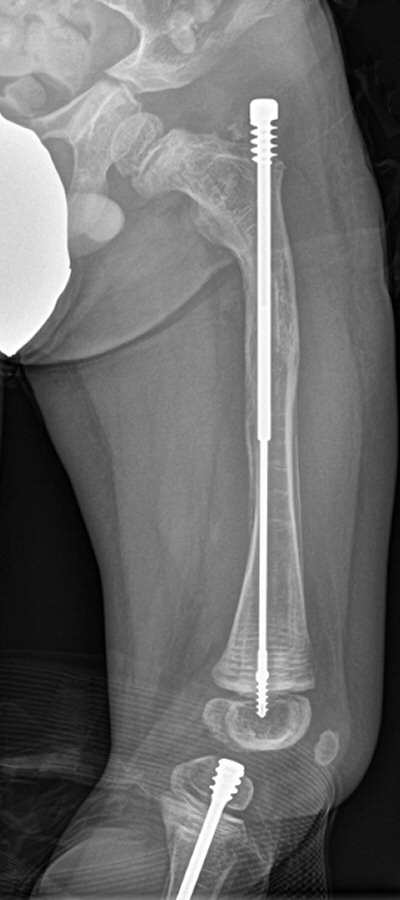

- Använd i första hand märgspikning med god upplinjering

- Profylaktisk märgspikning av långa rörben

Barn med osteogenesis imperfecta vid 6 månader, 2 år resp. 7 år